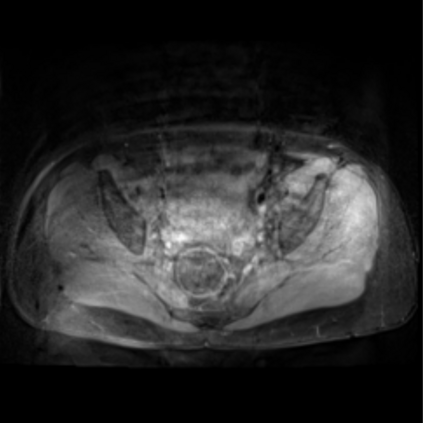

Motion artifacts are a primary source of magnetic resonance (MR) image quality deterioration with strong repercussions on diagnostic performance. Currently, MR motion correction is carried out either prospectively, with the help of motion tracking systems, or retrospectively by mainly utilizing computationally expensive iterative algorithms. In this paper, we utilize a novel adversarial framework, titled MedGAN, for the joint retrospective correction of rigid and non-rigid motion artifacts in different body regions and without the need for a reference image. MedGAN utilizes a unique combination of non-adversarial losses and a novel generator architecture to capture the textures and fine-detailed structures of the desired artifacts-free MR images. Quantitative and qualitative comparisons with other adversarial techniques have illustrated the proposed model's superior performance.

翻译:移动文物是磁共振(MR)图像质量恶化的一个主要来源,对诊断性能产生强烈影响。目前,MR运动的校正要么是预期性的,借助运动跟踪系统,要么是追溯性的,主要是利用成本昂贵的计算迭代算法。在本文中,我们使用名为MedGAN的新颖的对抗性框架,联合追溯性地校正不同身体区域的硬性和非硬性运动文物,而不需要参考图像。 MedGAN利用非对抗性损失和新型生成器结构的独特组合来捕捉无MR图象的纹理和精细详细结构。 与其他对抗性技术的定量和定性比较展示了拟议模型的优异性表现。